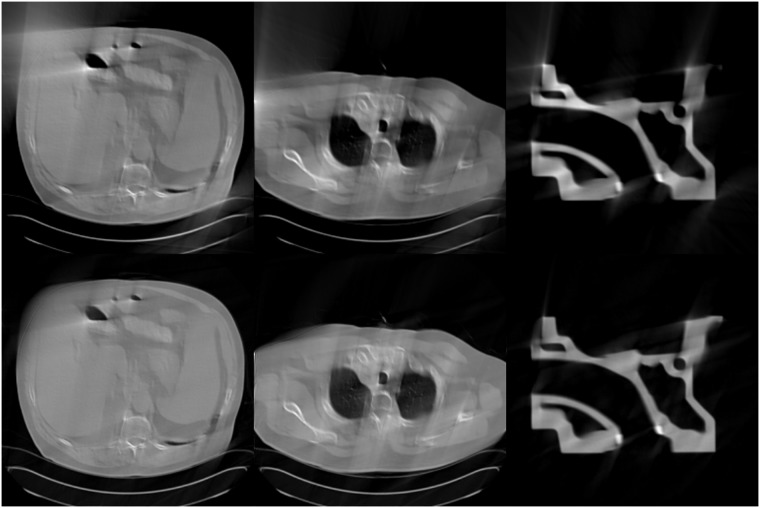

Inspired by their work, we use SART method to obtain the initial image for the well-trained U-net to process limited-angle image reconstruction for TCT. The reason why we do this is that the SART method is better than the FBP method in the limited-angle TCT scanning mode (as shown in Fig 4). Therefore, the quality of the training set for the proposed algorithm is better than that of the FBPConvNet method. Moreover, in the field of deep learning, the quality of the training set plays a decisive role in the final result. Hence, the proposed algorithm which is called SARTConvNet is more effective than the FBPConvNet method for limited-angle TCT. In addition, if we use the image reconstructed by TV method as the input image of the CNN, we need to manually adjust the regularization parameters of the TV method which is a difficult job and different images have different optimal parameters.

Fig 4. Reconstruction results for the scanning range [0°, 120°].

The first row is the images reconstructed by the FBP method, and the second row is the images reconstructed by the SART method.